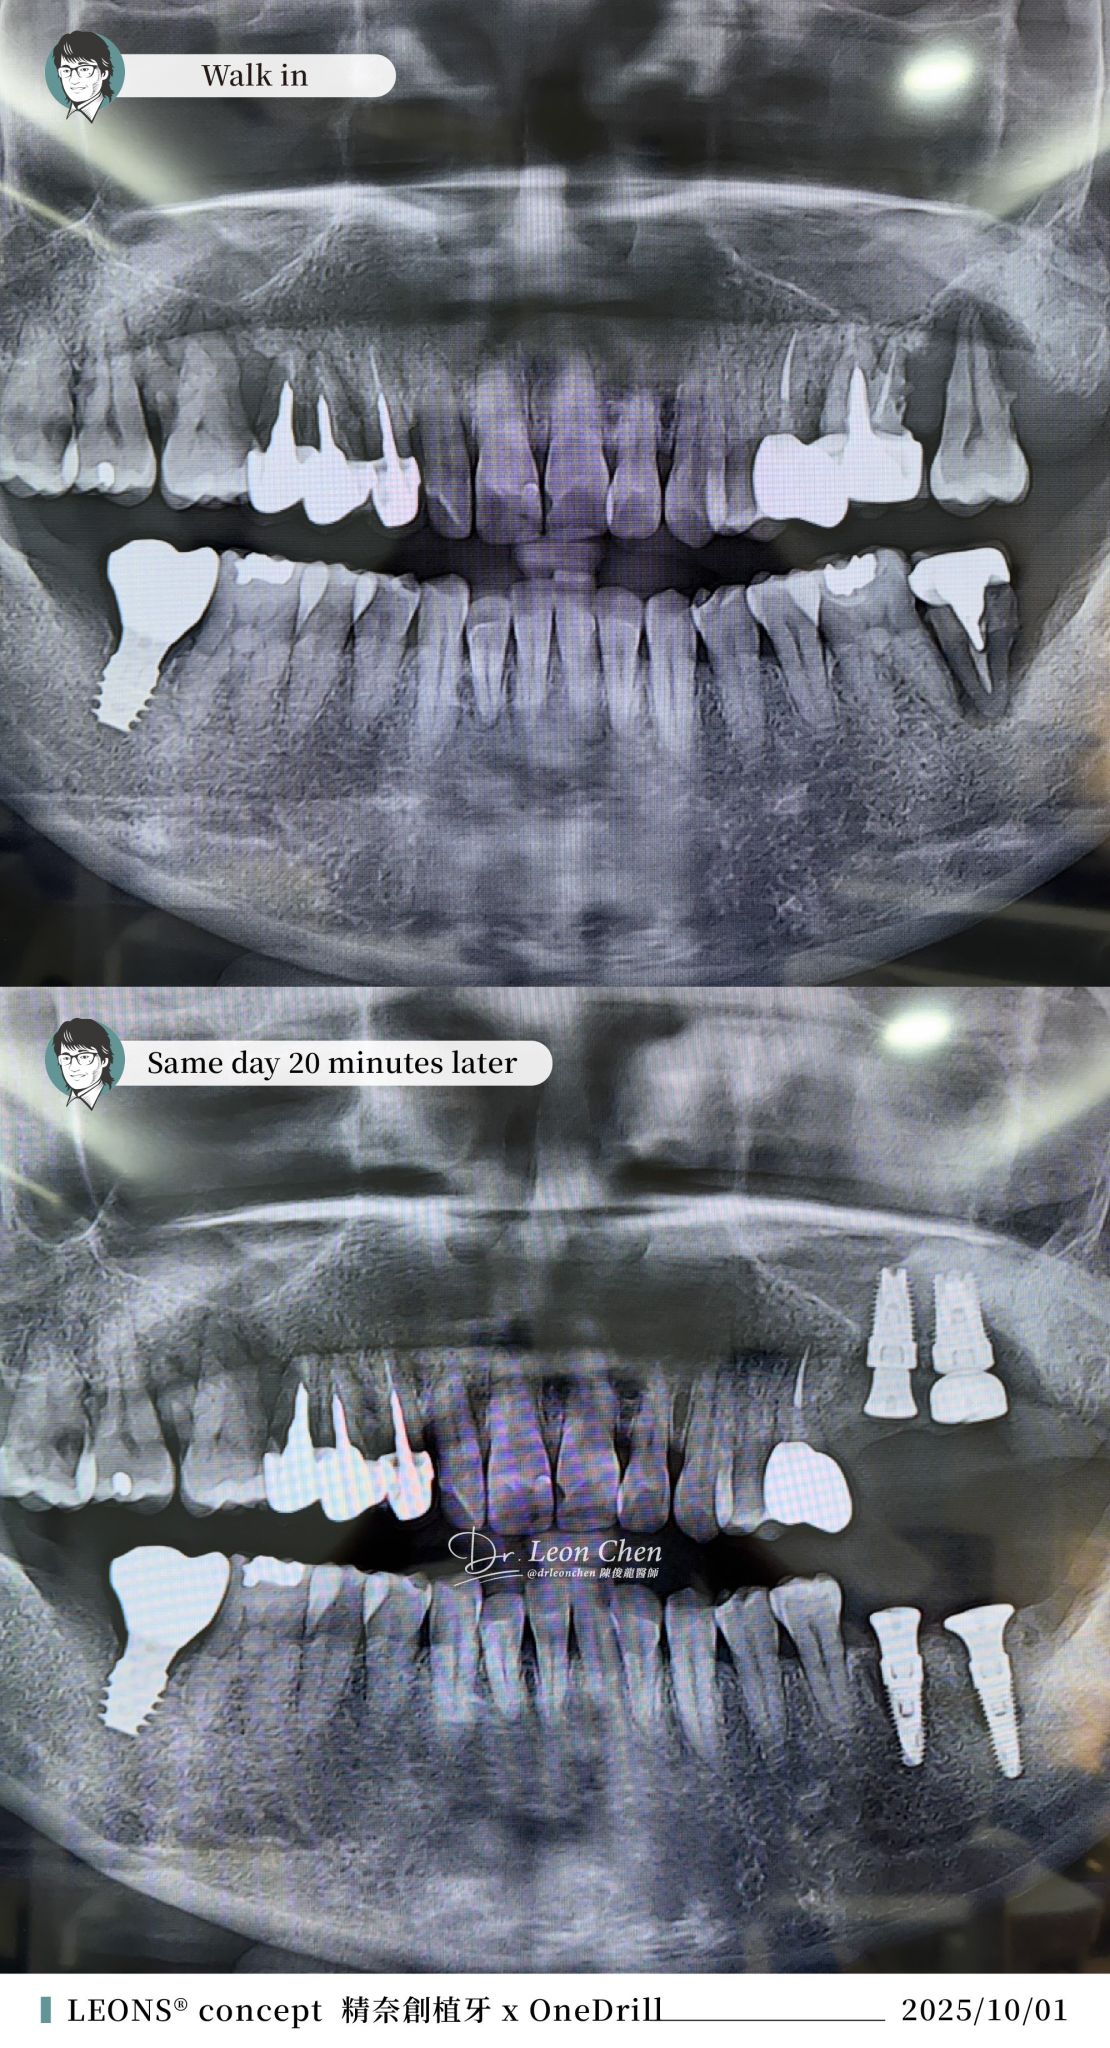

精奈創一鑽植牙系統團隊|重拾植牙勇氣

這位病人,曾經在別家診所做過植牙,雖然手術非常成功,但過程讓病人感受太痛苦,讓他從此對「植牙」充滿恐懼。

後來其他牙齒陸續出問題,他寧願忍痛,也不願再治療。直到實在撐不住了,才鼓起勇氣找到陳博士。

植牙當天,陳博士只花了半個小時,順利完成所有治療。

「陳俊龍博士整套 LEONS Concept 精奈創一鑽植牙」手術少,創傷小,恢復快!沒有併發症;適合各類患者,不需停藥,也能安全接受治療。